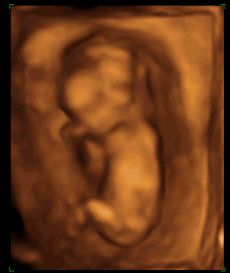

E-lona krótkie to u mnie w ramach każdej wizyty, tak ok 5 min, szybkie pomiary do szacunku wagi i kontrola przepływów. Dostaje tylko potem wydruk z pomiarami. A długie to te 3 zalecane: prenatalne, połówkowe i w okolicy 32tc i te u mnie trwają 30-40 min i wtedy dostaje duzo zdjęć i filmik

Teraz bede miała wizyte w 30 tc wiec nie wiem czy zechce już robic to długie czy zrobi tylko takie na szybko i umówimy sie na konkretniejsze końcem sierpnia.

zdecydowalam sie na to badanie bo chodze do gina na kase chorych wiec nie wszystkie badania mam dokladnie porobione... nawet nie znam wagi dzidziusia:-( i do tej pory nie chciało wcale pokazac co ma pomiedzy nozkami (wstydnis

). Mam nadzieje ze na 4d rozłoży ładnie nozki i pochwali sie czym je Bozia obdarzyła